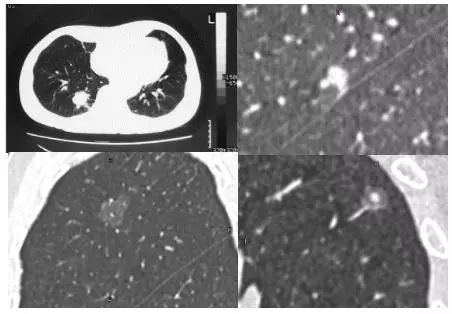

密度分类

实性肺结节(solid nodule),间质血管都看不见(左上图),亚实性肺结节(subsolid nodule)包括纯磨玻璃结节(pure ground-class nodule,pGGN)(左下图),还有混杂性结节(mixed ground-glass nodule,mGGN),也称部分实性结节(part solid nodule),表现为间质样改变,中间实性,周围是磨玻璃样。